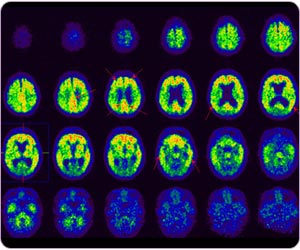

11C 標記PIB 正電子掃描腦部:病人在post cingulate gyrus, frontal lobe, precunes, parietal lobe, temporal lobe區域都呈現澱粉斑塊,診斷為阿耳滋海默氏病。